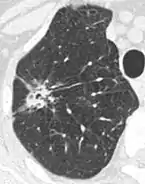

Chest X-ray showing a solitary pulmonary nodule (indicated by a black box) in the left upper lobe. | |